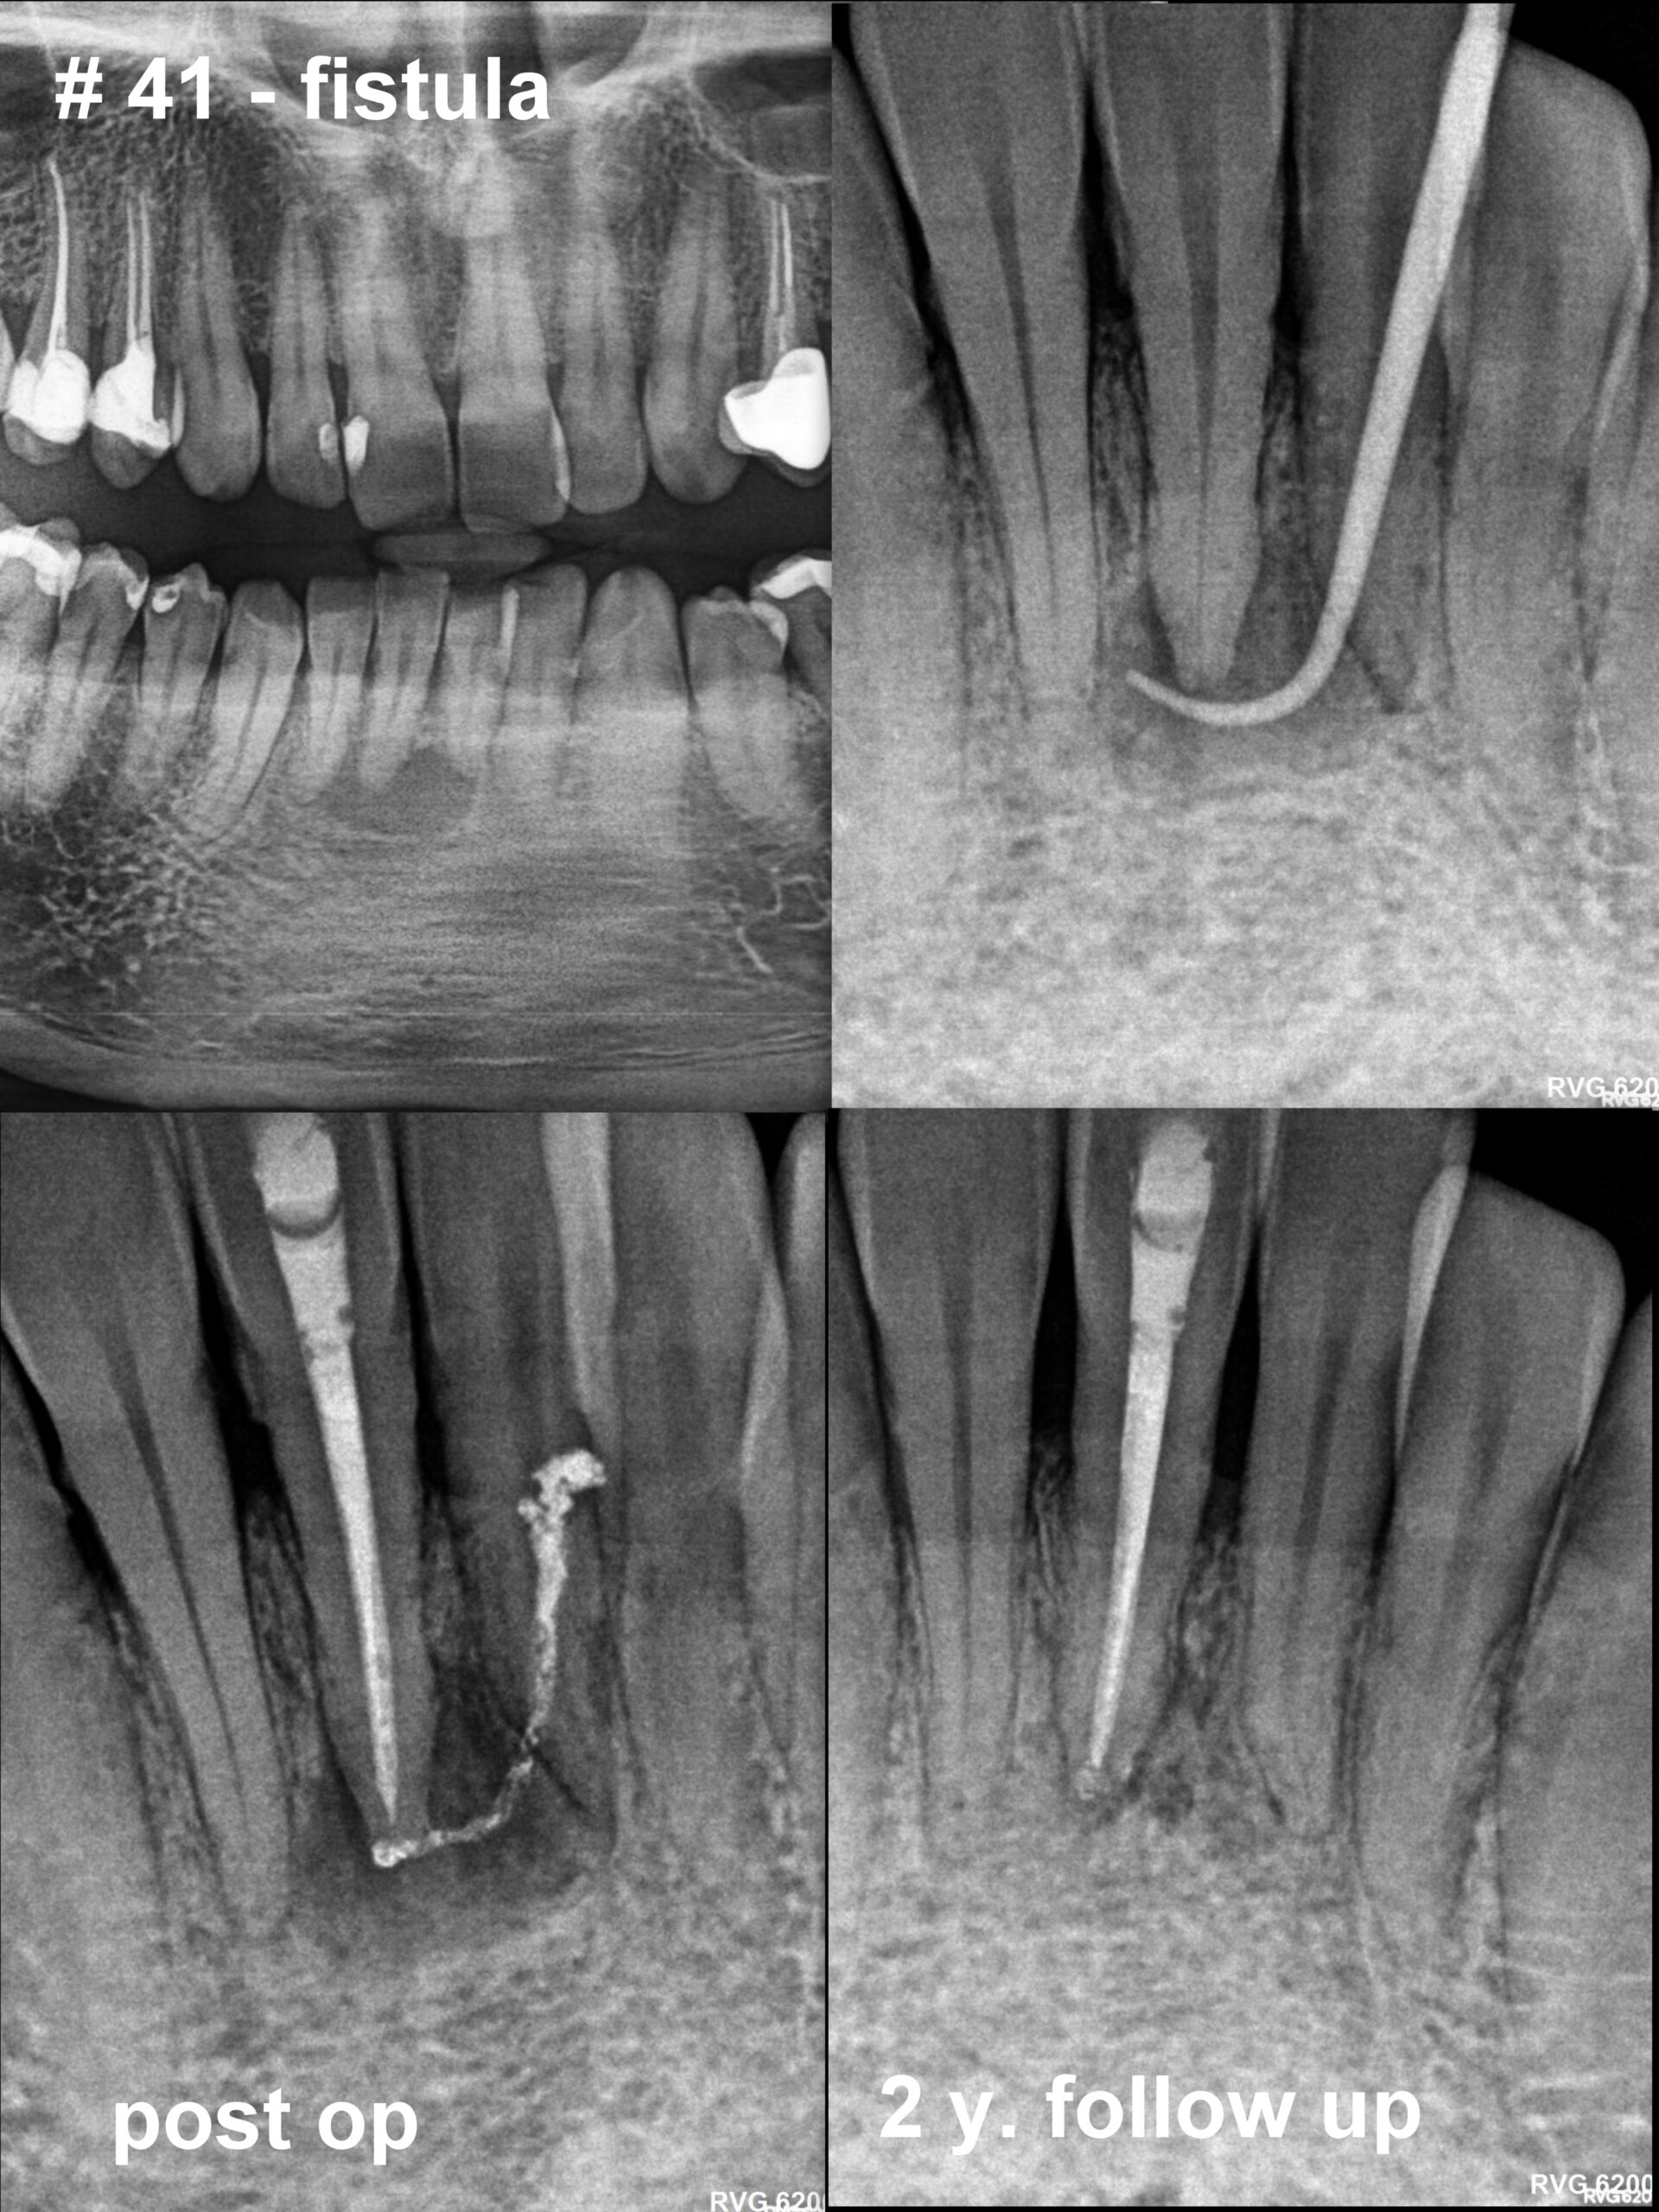

Poniżej prezentuję efekty leczenia kanałowego pod mikroskopem stomatologicznym. Wybrałam przypadki trudne i bardzo trudne. Do najbardziej czasochłonnych należy usuwanie z kanałów złamanych narzędzi i metalowych wkładów koronowo – korzeniowych oraz udrażnianie kanałów zobliterowanych.